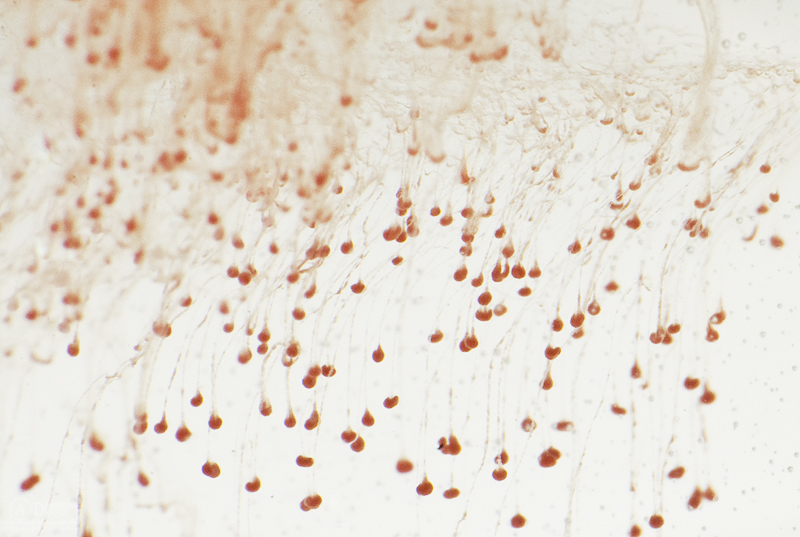

În fotografiile de mai jos puteţi vedea câteva globule roşii în timpul procesului de osmoză.

Bravo, aşa e! O picătură de sânge în soluţie de sare de bucătărie cu concentraţie 0.89%. A apărut astfel procesul de osmoză. Ce vezi aici sunt globulele roşii. 🙂